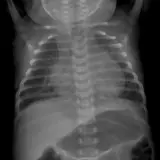

Over 2,100 interactive radiology cases, curated by radiologists for your level of training. Scroll, window, and view cases full screen โ€” just like on PACS. Click linked findings in each writeup to jump straight to them on the image. Cases include sample reports, a focused discussion section, original illustrations, and videos.

Casi completamente interattivi con gli strumenti che ti aspetti su un PACS: scroll, windowing, zoom, pan, misurazioni, ROI e modalitร  a schermo intero.

Annotazioni dettagliate evidenziano i reperti chiave direttamente sui casi. Clicca sui reperti collegati nella descrizione del caso per saltare alla loro esatta posizione sullo scan.